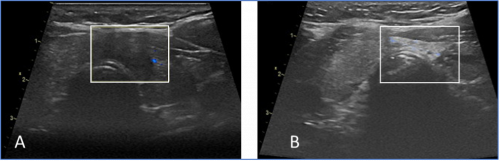

Das Schilddrüsenkarzinom (A) im weißen Rechteckt ist nach der Therapie nicht mehr nachweisbar (B). In Deutschland hat Prof. Korkusuz die meisten Ablationen von Schilddrüsenkarzinomen erfolgreich durchgeführt.